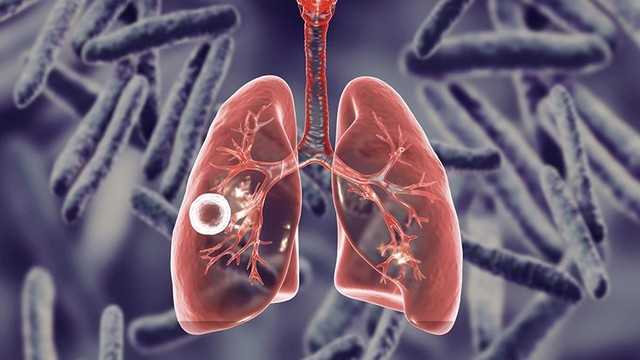

Tràn máu màng phổi là một tình trạng nghiêm trọng có thể đe dọa tính mạng nếu không được điều trị kịp thời. Những người bị chấn thương ở ngực cần được kiểm tra khả năng tràn máu màng phổi để hạn chế nguy cơ diễn tiến của biến chứng trên phổi. Một số ít trường hợp cũng có thể xảy ra do những nguyên nhân khác liên quan đến những tình trạng bệnh lý tại phổi.